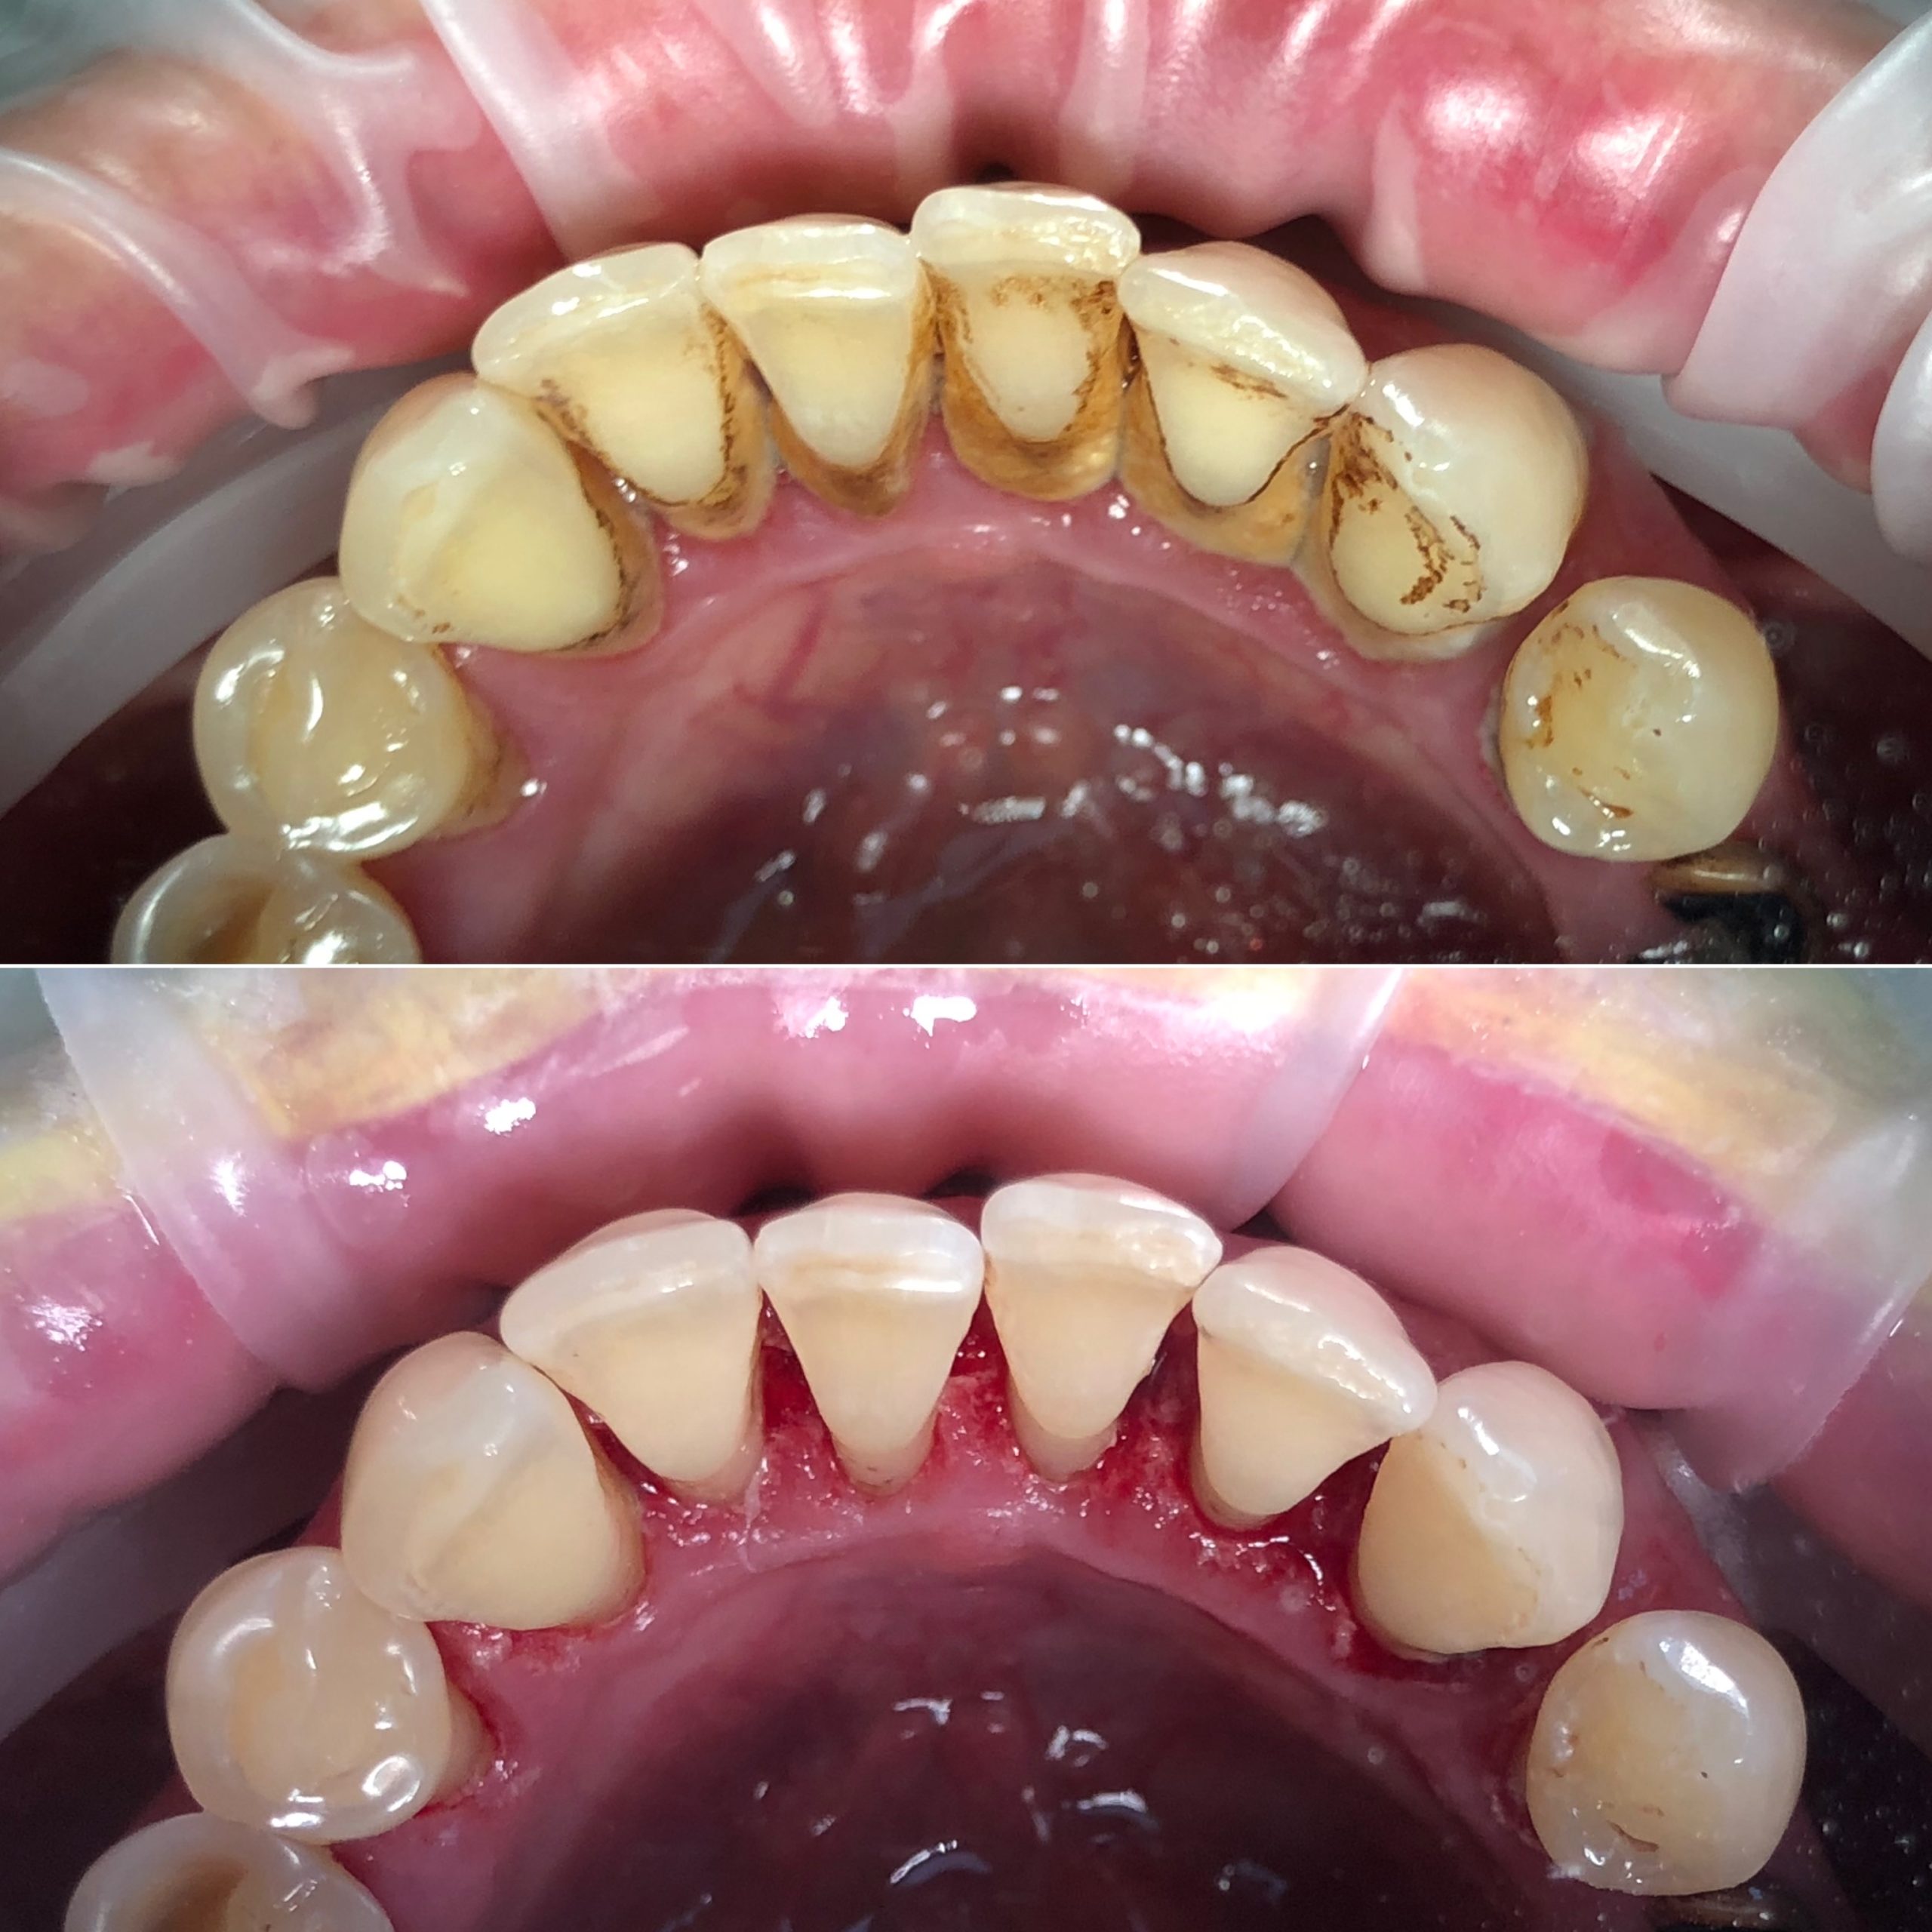

• Профессиональная гигиена полости рта и подбор индивидуальных средств гигиены, профилактика стоматологических заболеваний

2023 год – «Вектор-терапия – одна из эффективных методик в пародонтологии» учебный центр DSpace

2024 год – «Системный подход к лечению пациентов с заболеваниями пародонта. Ручные инструменты и SRP-терапия» Юрий Гринюка